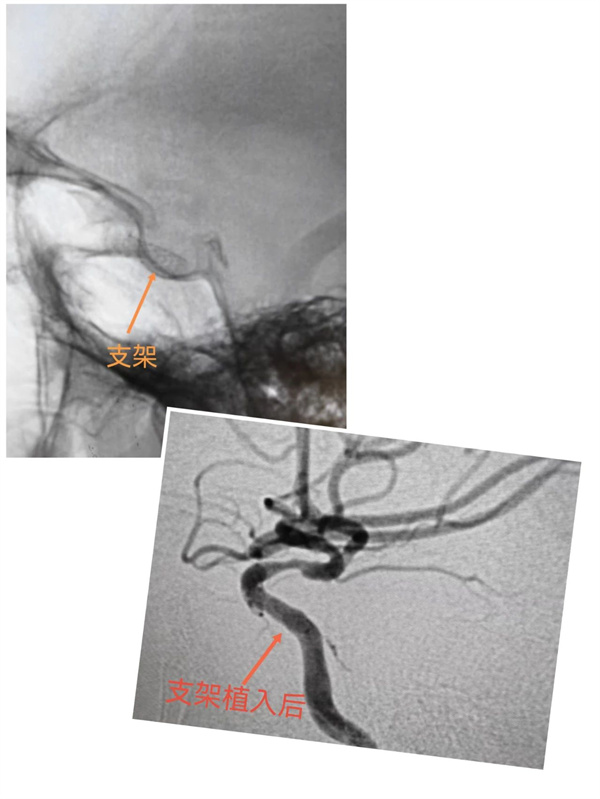

入院后,以李金亮主任为首的神经外科团队组织科内会诊,讨论后在局麻下行经股动脉全脑血管造影术。脑血管DSA造影提示:右侧颈内动脉C5段重度狭窄,狭窄率约80%,C6段轻度狭窄,狭窄率约40%。

经过多学科会诊,建议积极处理患者右侧颈内动脉狭窄,为患者施行右颈内动脉支架植入术,以减少脑梗塞发生的风险。